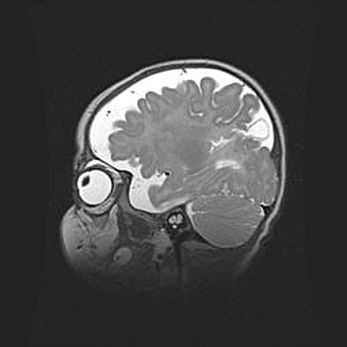

Неполная лизэнцефалия (пахигирия). Открытая гидроцефалия.

Возраст: 17 дней

Вес: 3110 г

Пол: мужской

Окружность головы: 33,5 см

Срок гестации: 35-36 недель

Лизэнцефалия—недоразвитие корковой пластинки и мозговых извилин в результате нарушения миграции нейронов коры. Поверхность мозговых полушарий гладкая. Микроскопически выявляется отсутствие нормальных слоев коры и скопление групп нейронов в подкорковом белом веществе.

Пахигирия—уменьшение числа вторичных извилин. В пораженном полушарии нервные клетки образуют толстый недифференцированный слой с неправильно расположенными нервными волокнами и группами гетеротопных клеток. Нервные клетки незрелые. Белое вещество истончено. При этом нередко аномально развит корково-спинномозговой путь.